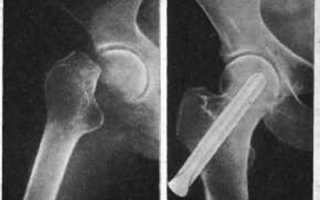

При соблюдении всех необходимых условий для срастания костных отломков происходит адекватная по времени консолидация перелома, которая может занимать от нескольких недель до нескольких месяцев. Например, кости голени срастаются примерно за 3 месяца, в то время как перелом шейки бедра требует около 6 месяцев. С увеличением возраста пациента процесс срастания кости ухудшается. Перелом шейки бедра может надолго ограничить подвижность пожилого человека, что приводит к серьезным осложнениям, таким как тромбоэмболия легочной артерии, застойная пневмония и пролежни.

Что такое признак консолидации?

Признаки консолидации перелома. Критериями заживления служат: отсутствие межотломковой щели, наличие однородной плотности костной мозоли, пересекающей линию перелома, визуализация восстановленного канала (вместилища костного мозга) и кортикального слоя на уровне повреждения.